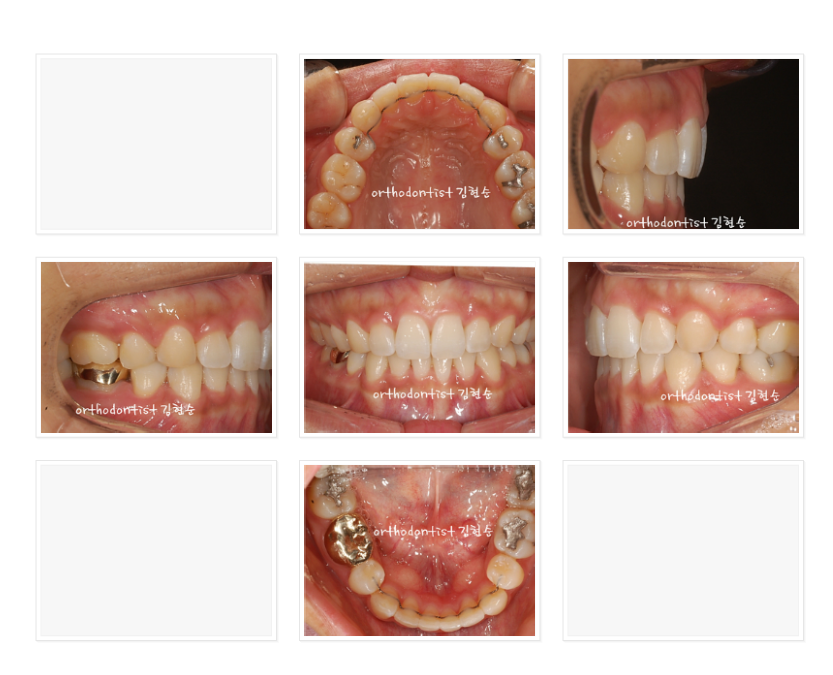

이 분은 앞 얼굴 및 전체적인 인상이 정말 아름다워지셨습니다.

다만 공개된 곳에서 정면 얼굴을 올리시는 것은 결례인 것 같아

차마 올리지 못해 아쉽네요.^^;